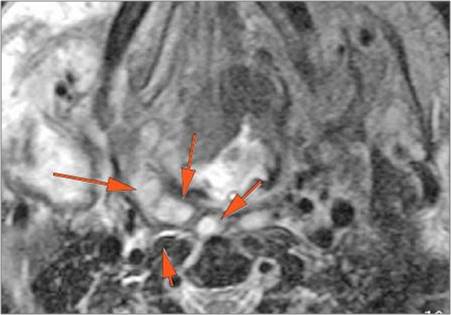

Retropharyngeal Lymph Nodes

If there is suppurative retropharyngeal adenopathy what is the maximum short axis dimension of the largest suppurative node. MEASUREMENT

There is edema within the adjacent deep neck, retropharyngeal and/or prevertebral spaces.

There is abscess within the adjacent deep neck, retropharyngeal and/or prevertebral spaces.